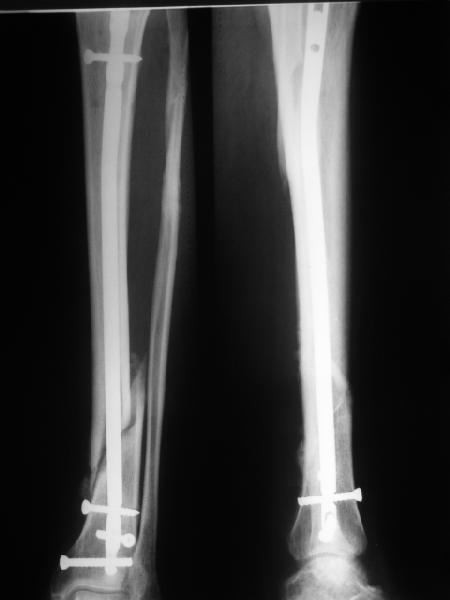

В Кемпбелле можно прочитать, что Fractures in the distal third of the tibia had the highest frequency of nail breakage.

Вообще, этот вопрос обсуждался давно, и еще в статье R. Bucholz (1987) про переломы гвоздей указывалось, что расстояние от ближайшего отверстия до перелома должно быть не менее 5 см, иначе есть угроза усталостного перелома. По литературе переломы гвоздей в нижней трети

tibia достигают 4,3%.

Посмотрев на клинический случай с винтообразным переломом ББ и МБ костей, возник вопрос о целесообразности динамизации фиксатора при подобном типе перлома.

Винтообразный перелом создает обширную зону межфрагментарного контакта, что является благоприятным условием для консолидации, если в ожидаемые 8-10 недель мозолеообразования не наблюдается, то динамизация приводит к *соскальзыванию* проксимального фрагмента- вторичному смещению, величина которого и определяется размером овального окна гвоздя.

Логичным, на мой взгляд, в подобной ситуации является не динамизация гвоздя, а смена гвоздя на больший размер с рассверливанием.

Динамизация скорее показана при поперечных/ short oblique типах, когда зона межфрагментарного контакта ограничена, нет риска вторичного смещения отломков.